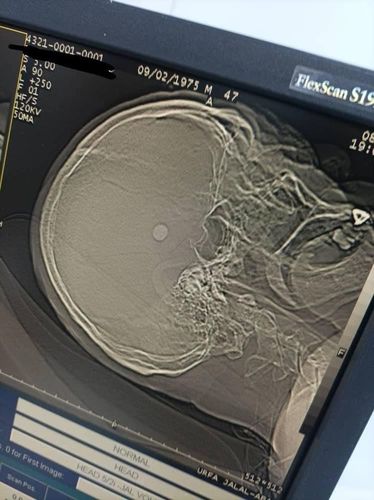

Neurosurgeons of the Jalal-Abad Regional Clinical Hospital performed an emergency complex brain surgery. Press center of the Ministry of Health of Kyrgyzstan reported.

The patient was admitted with an open penetrating wound to the head — the bullet was in the frontotemporal lobe on the right.